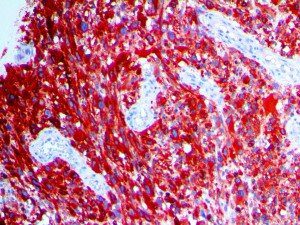

It is the ICU physician who is most likely to witness one of the deadliest manifestations of the abnormal immunological response, the cytokine storm syndrome (CSS). This response is also referred to by some as the cytokine release syndrome (CRS). CSS is characterized by continuous activation and expansion of macrophage and lymphocyte populations, which secrete large amounts of cytokines, causing the cytokine storm. This massive cytokine release is akin to hemophagocytic lymphohistiocytosis (HLH) disease, a syndrome characterized by initial unchecked and persistent activation of cytotoxic T lymphocytes and NK cells.

Clinical and laboratory manifestations of HLH include fever, enlarged liver and/or spleen, neurologic dysfunction, coagulopathy, liver dysfunction, cytopenias (i.e., low levels of erythrocytes, leukocytes, and/or platelets), hypertriglyceridemia, hyperferritinemia, hemophagocytosis, and eventually diminished NK cell activity as the immune system becomes progressively paralyzed. HLH can be familial (primary HLH) or secondary to another disease process (sHLH), such as rheumatic disease, in which it is referred to as macrophage activation syndrome (MAS, characterized by elevated ferritin).